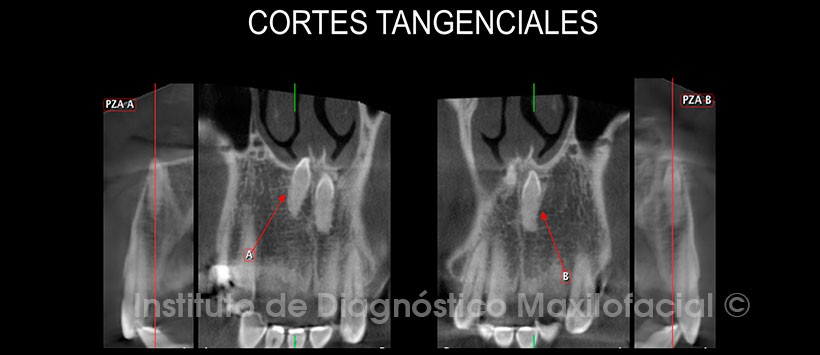

La tomografía computarizada de haz cónico mediante los cortes transaxiales y tangenciales nos muestra la clara presencia de dos piezas supernumerarias a las cuales denominaremos A y B; las mismas que se encuentran en una posición superior a las piezas 11 y 21; y que además se hallan próximas a la tabla ósea vestibular. Se aprecia también la posición invertida de ambas piezas supernumerarias y la estrecha relación de la pieza supernumeraria A con el piso de fosa nasal (Fig. 2 y 3).